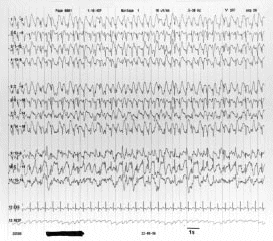

Figura 14.- Trazado electroencefalográfico de un "estado de mal" epiléptico postanóxico. Todo el trazado está ocupado por ondas puntiagudas (puntas).